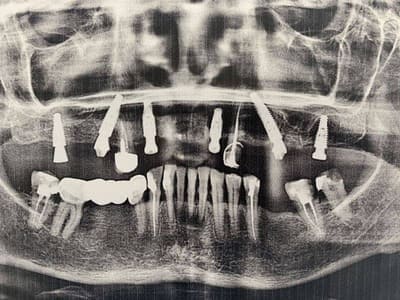

Удаление семи зубов на верхней челюсти. Одномоментная имплантация системой Neodent 6 зубов, предназначенная для немедленной нагрузки (изготовление временных коронок в день имплантации). В день имплантации сняли оттиски для временного протезирования Telio Cad. Конструкция была установлена через 2 недели после имплантации.

До

После